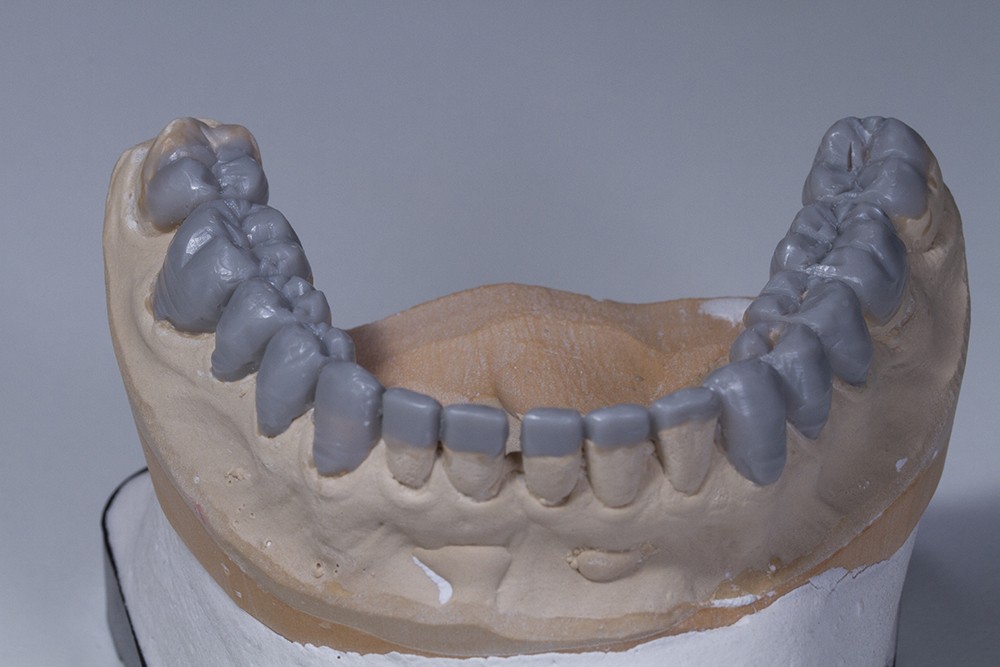

Dans un deuxième temps, un wax-up global permet de restaurer les courbes d’occlusion. Il est à noter que la présence d’égressions dentaires, faute d’antagoniste ou d’anciennes restaurations prothétiques inadaptées, crée des usures inégales au sein de la cavité buccale. Aussi, la présence de zones non recouvertes par le wax-up dans les secteurs postérieurs est courante, permettant ainsi la préservation de zones amélaires majeures pour le collage (fig. 2).

Le wax-up est le point de départ pour la réalisation de temporisations en technique d’isomoulage. Pour cela, le repositionnement de la clé en silicone s’effectue grâce à la réalisation de butées d’enfoncement sur des zones non waxées ou volontairement déwaxées (fig. 3).